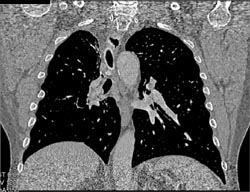

Neurogenic Sarcoma